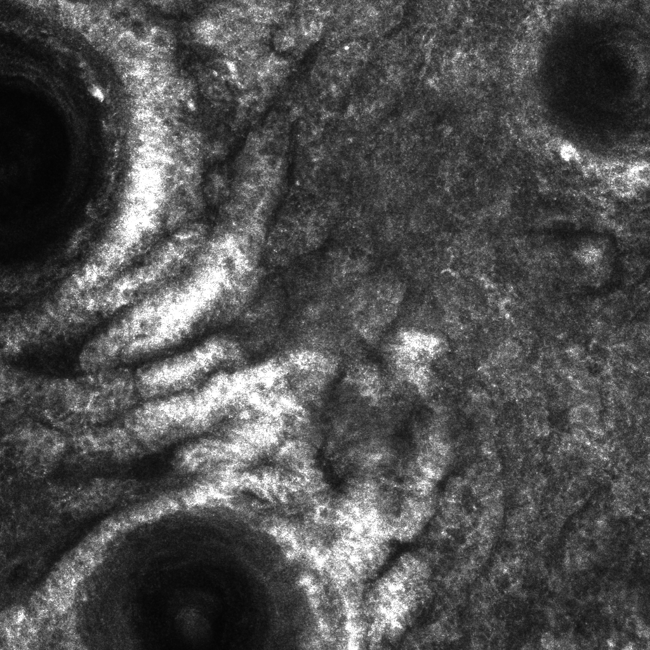

Please review the clinical and dermoscopy images below. What are the three potential diagnoses of flat pigmented lesions on the face, and how do you differentiate between them?

This lesion is a solar lentigo. Confocal imagery: